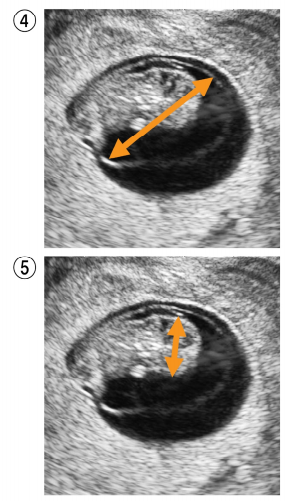

4 妊娠初期の経腟超音波像別冊No. 1 ①〜⑤を別に示す。 分娩予定日を決定するために有用な計測部位はどれか。 (A)① (B) ② (C)③ (D) ④ (E)⑤